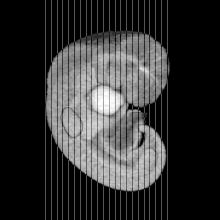

Carnegie Stage 14 (32 post-ovulatory days)

Most embryos at stage 14 are approximately 32 postovulatory days old and measure 5-7 mm in length. Distinguishing criteria for this stage include an open lens pit with invagination of the lens disc and elongated and tapering upper limb buds. The otic vesicle with a well-defined endolymphatic appendage is also a hallmark of this stage.

MRI Slice Selector

Mouse: click on a line below to select a view

Finger: tap a line below with a very light touch